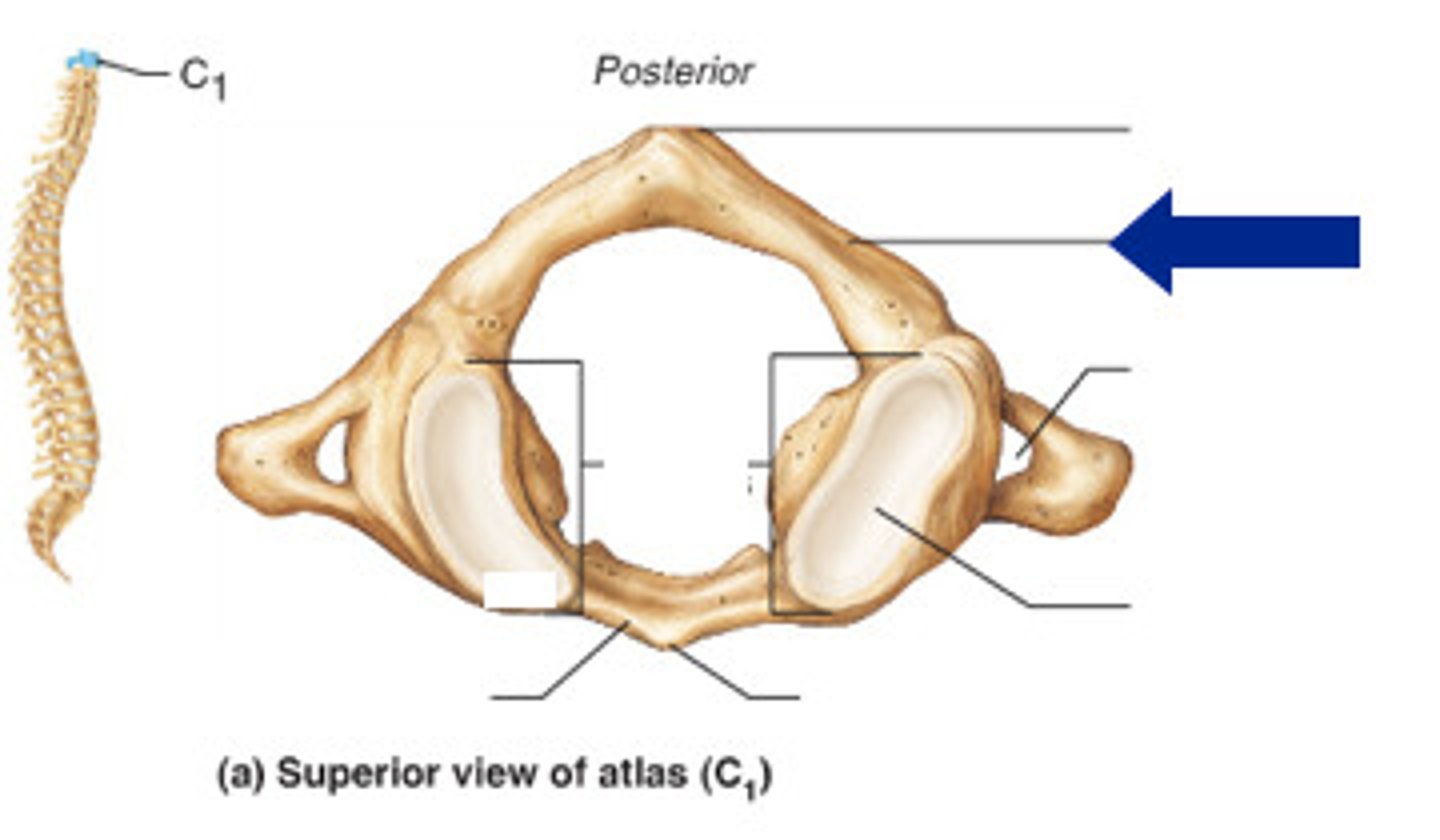

transverse formen (cervical)

superior articular facet of occipital condyle

vertebral formen

posterior arch

posterior tubercle

atlas C1

what vertebra is considered the atlas

hold head up

what is the purpose of C1

what vertebra is visually a flat bone